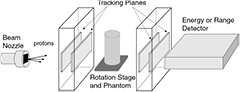

A contemporary pCT scanner generally takes the form illustrated in figure 2 [37]. Thin tracking detectors measure the particle trajectories both entering and exiting the phantom5, from which the 'most likely path' (MLP) through the phantom can be estimated particle by particle. Note that a single layer in the front tracker would be sufficient if the incoming proton direction were well known. The second tracker is followed by an energy or range detector, usually in which the particles stop so that their residual energy or range can be measured. The beam is either fanned out into a cone to cover the instrument aperture (for example, by scattering in a thin foil) or else scanned across the aperture by magnets. The instrument must rotate around the phantom, or more easily the phantom can be rotated within the instrument, by at least  , either continuously or in discrete steps. For each particle, the instrument must provide the geometric path through the phantom together with the integrated energy loss, most conveniently in the form of the WEPL.

Figure 2. Schematic of a typical contemporary pCT scanner designed to measure individual proton histories.